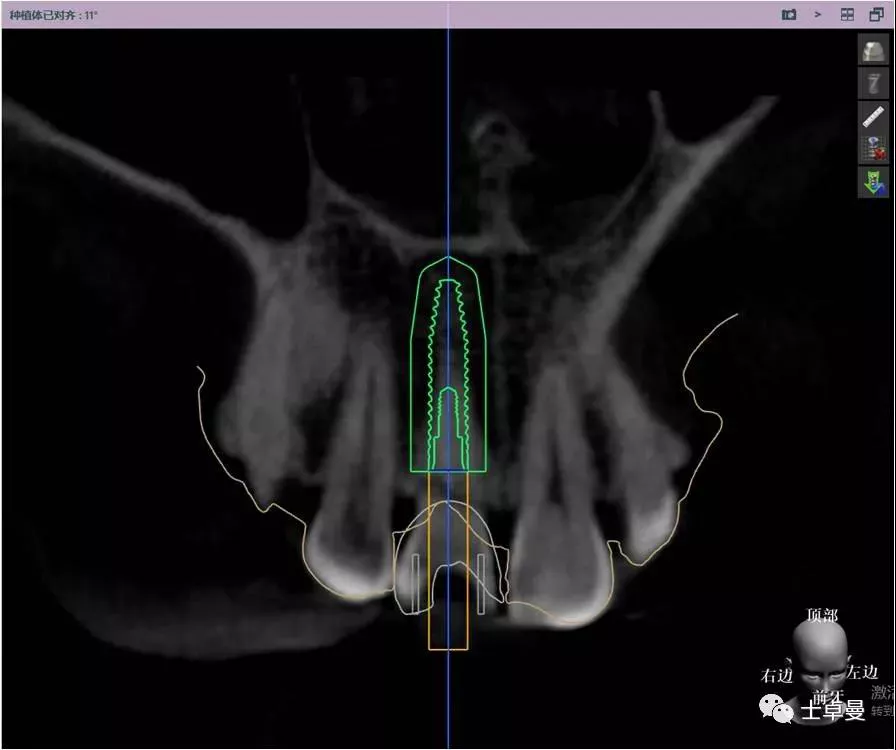

影像学检查,CBCT显示

· 11根管内充填致密,根尖未见明显阴影,根长约12mm;

· 唇侧牙槽骨完整,厚度约1.2mm;

· 根尖区剩余骨量约7mm。

就位种植外科导板

指示杆观察备孔三维位置

术后即刻CT示,种植体植入位置理想